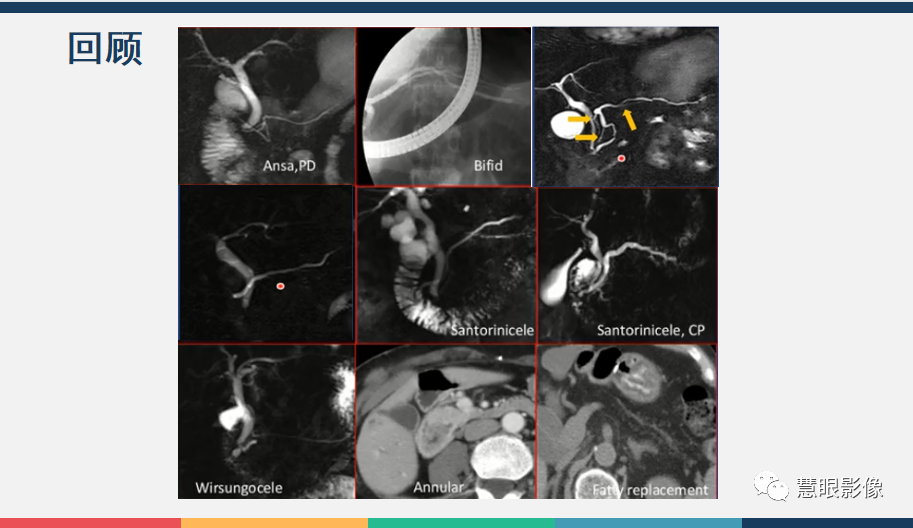

【PPT】胰腺解剖变异、发育异常及相关病变影像评估-4